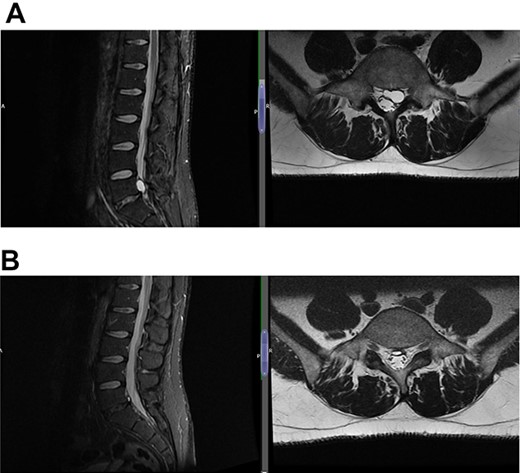

(A) Case 2—initial MRI shows a slightly unusual abnormality associated with the L5-S1 compressing the left transiting S1 nerve root and is almost certainly a fragment of extruded/sequestered disc, and (B) case 2—updated MRI shows a significant decrease in the previously seen cystic lesion at L5-S1 level now measuring 4 mm (AP diameter, previously 11 mm).

(A) Case 3—an early MRI demonstrates at L5/S1 level moderate diffuse disc bulge is seen with early bilateral facet joint degenerative changes; there is irritation of the L5 nerve roots bilaterally, and at L5/S1 level moderate left posterolateral disc bulge is seen irritating the S1 nerve roots bilaterally left more than right, and bilateral facet joint degenerative changes also noted at this level, and (B) case 3—a later MRI, the cystic changes noted at the L4-L5 level which clearly shows a connection with the intervertebral disc.